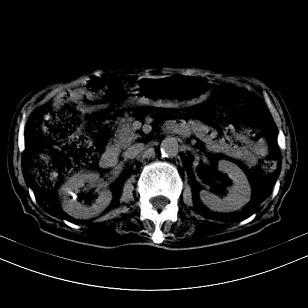

标题: CT19407:肝内还是肝外原发性肿瘤??

男,63岁,高血压病史40余年,

肝内多发低密度找;转移瘤?

考虑右肝后叶肝癌(部分外生)伴肝内多发性转移;右侧肾上腺区恶性肿瘤并肝转移待排。

考虑右肝后叶肝癌(部分外生)伴肝内多发性转移

考虑肝右叶变异肝癌并肝内转移

考虑右肝后叶肝癌(外生型)伴肝内转移。

肝右叶外生性肝癌,伴肝内转移

考虑肝右后叶肝癌(部分外生)伴肝内多发性转移;不排除右侧肾上腺区恶性嗜铬细胞瘤并肝转移。